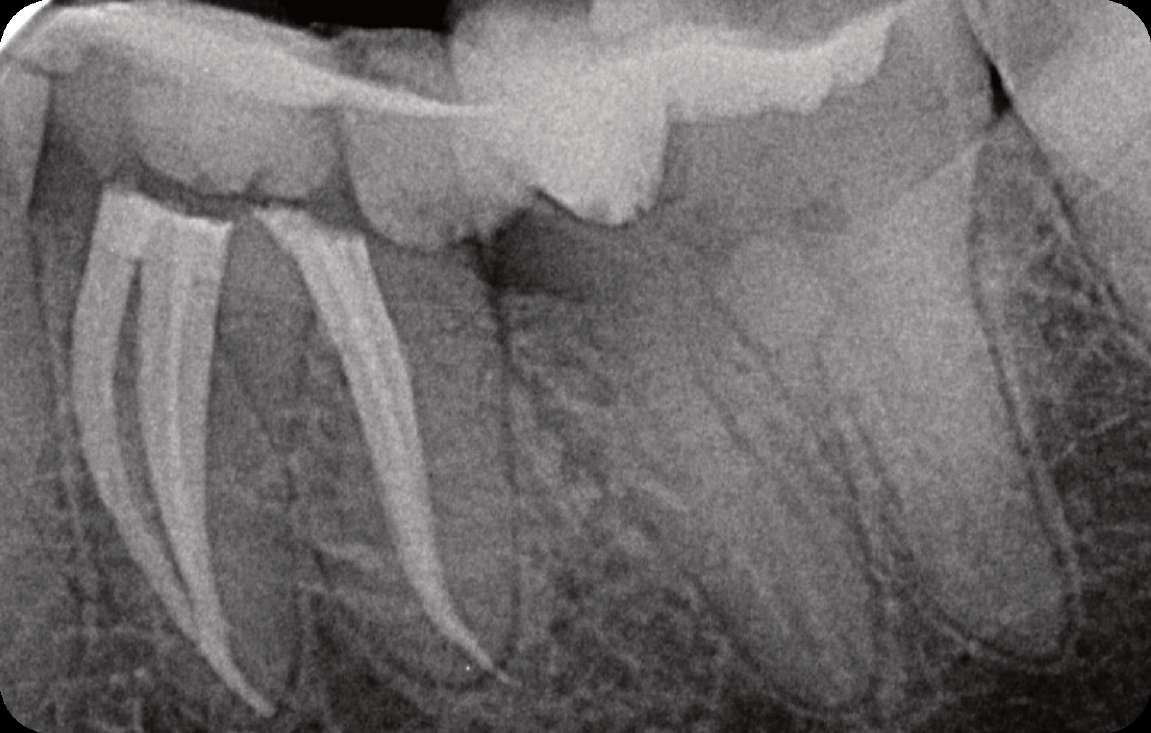

Präoperativ

Der erste untere, linke Backenzahn zeigt einen Zerfall auf dem distalen Teil mit dem Symptom einer irreversiblen Pulpitis. Zuerst wird der Karies entfernt und der Zahn wird mit einer temporären Füllung wieder aufgebaut. Danach wird der Kofferdam platziert und der Zugangshohlraum steht.

Vier Kanäle wurden mit dem SX EdgeTaper Platinum eröffnet. Auch der koronale Teil wurde mit dem S1 EdgeTaper Platinum erweitert. Arbeitslänge und Durchgängigkeit werden mit einer #10 K-Feile erreicht. Die A #15 K-Feile wurde verwendet, um Länge und Durchgängigkeit zu gewährleisten. Dank der Technologie von EdgeNedo war ich im Stande, die Feile für eine komfortable Formgebung vorzuformen, auch wenn die Öffnung reduziert wurde. S1, S2, F1 und F2 EdgeEndo Platin wurde bis zur gesamten Länge des Kanals eingebracht.

Während der Isthmus-Reinigung zeigte sich zwischen den mesialen Kanälen ein zusätzlicher Kanal. Die Formgebungsphase erfolgte schnell und effizient dank SX zum F2.

Das Röntgenbild zeigte eine große Länge und einen gemeinsamen Ausgang für zwei der drei mesialen Kanäle.

Die Wurzelfüllung erfolgte mit einer einzigen Kegeltechnik unter Verwendung des BUSA EndoSequence Bioceramic Sealer. Das Post-OP-Röntgen zeigt sehr hohe Dichte in der gesamten Länge der Wurzelfüllung.